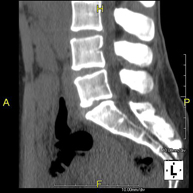

Prova radiològica que consisteix en obtenir imatges de les vèrtebres lumbars d'alta definició anatòmica, mitjançant l'ús d'un equip de TC (Tomografia Computaritzada). Indicacions: dolor lumbar sense / amb irradiació a les cames, dificultat per caminar, traumatisme. - TC de sacre-còccix